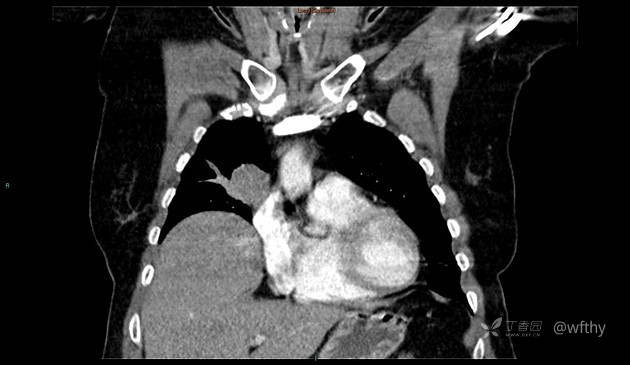

病例女65,头部肿块